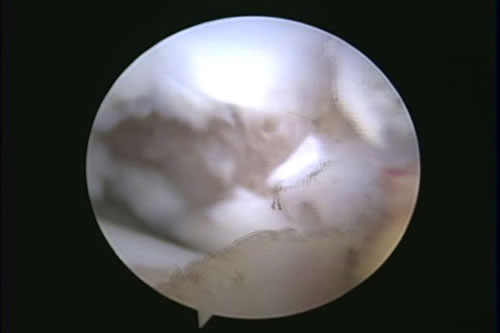

OCD(離断性骨軟骨症)

OCD(離断性骨軟骨症)とは

大腿骨骨頭の関節軟骨が成長障害により厚みを増し、損傷を受けやすくなり、軟骨が浮きあがりはがれることで痛みを生じます。

診断

レントゲン検査、関節鏡検査

治療

OATS(自家骨軟骨移植)など。軟骨の欠損部に別の部位から採取した本人の正常な軟骨を移植し、関節面での接触を良くし、痛みを取り除きます。大型犬の成長期の跛行は消炎鎮痛剤等による対症療法ですませず、跛行原因の早期診断、早期治療が重要です。